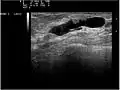

They are the most common cause of bloody nipple discharge in women age 20-40 and generally do not show up on mammography due to their small size. They may be detectable on ultrasound. A galactogram is the most definitive test but is somewhat invasive.